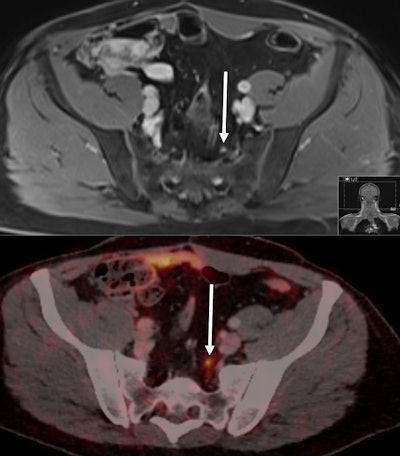

In fact, Sawicki and colleagues are well-versed in the utility of Ga-68 PSMA to assess cancer cases. Their 2017 study combined the radiopharmaceutical with PET/MRI to better detect and classify local lesions and distant metastases in women suspected of having recurrent pelvic cancer than MRI alone. They went on to advocate that the hybrid modality be considered a valuable alternative for whole-body staging of patients with suspected recurrent disease.

In the current study, the researchers prospectively enrolled 28 consecutive male patients (mean age, 65.3 ± 9.0 years) with newly confirmed cases of prostate cancer recurrence (PSA ≥ 0.2 ng/mL) who had undergone radical prostatectomy. All the patients underwent both whole-body 1.5-tesla MRI scans (Magnetom Avanto, Siemens Healthineers) with a dedicated pelvic imaging protocol and Ga-68 PSMA PET/CT scans (Biograph mCT 128, Siemens). PET/CT was performed one hour after intravenous injection of Ga-68 PSMA (mean, 166 ± 35 MBq). The scans took place within a limited time of 11 (± 10) days. The average PSA level in the patients at the time of imaging was 2.09 (± 1.95) ng/mL (range, 0.2-9.9 ng/mL).

Ga-68 PSMA PET/CT detected prostate cancer lesions in 20 of the 28 patients (71%) with disease recurrence, compared with MRI's detection of prostate cancer lesions in 11 patients (39%) with recurrence. The difference between the two modalities in this per-patient comparison was statistically significant (p = 0.0167).

Among the 20 patients with disease recurrence, there were a total of 56 prostate cancer lesions. Ga-68 PSMA PET/CT found all 56 of them (100%), compared with whole-body MRI, which detected only 13 prostate cancer lesions (23%), missing 43 (77%) lesions. Again the difference in performance was statistically significant (p < 0.001), and there were no false-positive findings among either modality, according to the researchers.